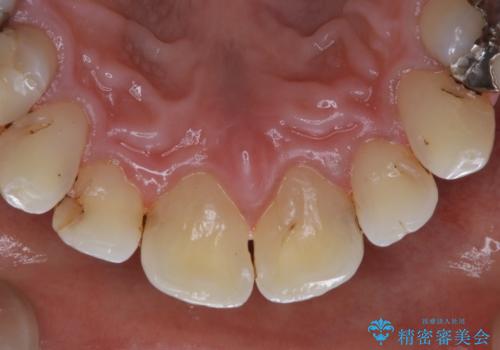

歯の表面に、茶色く色が残っている所がありますが、これは詰め物の変色の所と、虫歯になっている所です。以前に、CR(コンポジットレジン)による虫歯治療がされています。

CRは経年的劣化や、着色してしまうことがあります。PMTCでクリーニングを行うと、古いCRが目立つことがあるため、気になる際は詰め替えを行います。

茶色くなっている部分が、着色なのか、劣化なのか、虫歯によるものなのかは判別が難しいことがあります。そのため、定期的にPMTCを行うことで状態の確認が的確に行えます。

また、治療が開始される前などにも、全体的にクリーニングを行いご自身本来の歯の色、状態を精密に確認することが大切です。